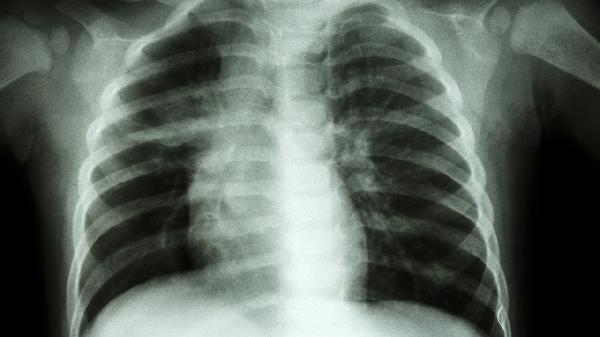

方中丹参具有改善肺部微循环的作用,能减轻粉尘沉积导致的肺组织充血及结节形成。部分患者在胸部CT检查时可发现肺部弥漫性小结节,服药后有助于抑制结节进一步增大。

使用矽肺宁片期间需定期复查胸部影像学及肺功能,避免接触粉尘环境。建议患者戒烟并保持适度有氧运动,饮食宜多摄入优质蛋白与维生素A丰富的食物如胡萝卜、动物肝脏,有助于肺泡上皮修复。出现发热或痰量突然增多时应及时就医评估是否需联合其他治疗。